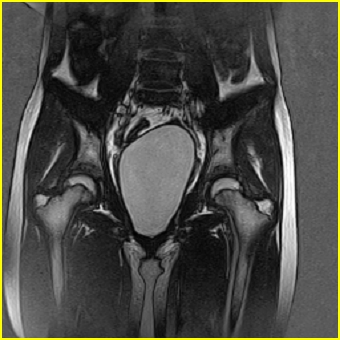

女、15岁、下腹疼痛2天,排尿困难1天。查体:处女膜闭锁,距处女膜约4至5cm处扪及一约5cm直径的圆形包块,张力较高,触痛明显、欠活动。b超提示子宫增大伴宫内增强回声团。

影像意见:子宫直肠陷凹积血。

更正影像意见:阴道积血。

处女膜闭锁,阴道积血

处女膜闭锁,阴道积血,子宫积血.

先天性处女膜闭锁,伴阴道积血,不除外先天性阴道粘液囊肿形成。

阴道积血,子宫积血.

子宫及阴道积血。

处女膜闭锁,伴子宫及阴道积血.